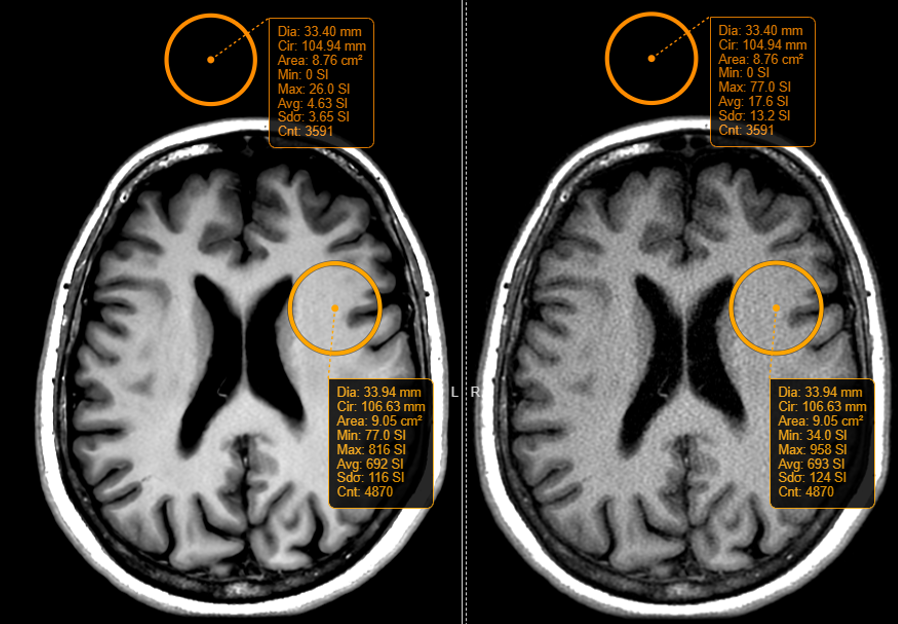

In Figures 4, 5, and 6, T1-weighted FLAIR, T2*-weighted FGRE, and T1-weighted FSE pairs of images are shown, respectively. Corresponding SNR gains were 379%, 680%, and 229%.

![[Uncaptioned image]](/html/2206.01082/assets/Figure_4.png)

Figure 4. Axial images of 2mm slice thickness acquired with a T1 fluid attenuation inversion recovery (FLAIR) pulse sequence. SNR gains of 379% were noted when the image was reconstructed through the deep learning-based reconstruction pipeline (left) compared to the conventional pipeline (right).